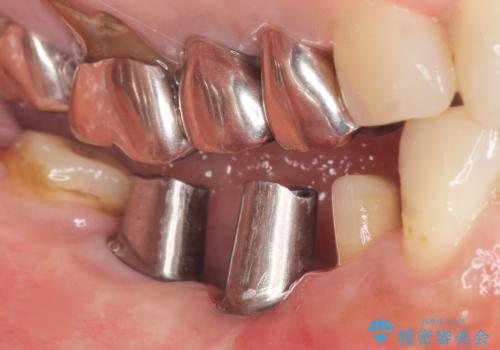

保存不可能な歯を抜去後、インプラント治療と根管治療を行いました。

- ¥1,177,000 (根管治療、土台、骨増生、インプラント・アバットメント×2本、仮歯・クラウン×3本) ※税込費用は治療当時の料金となります